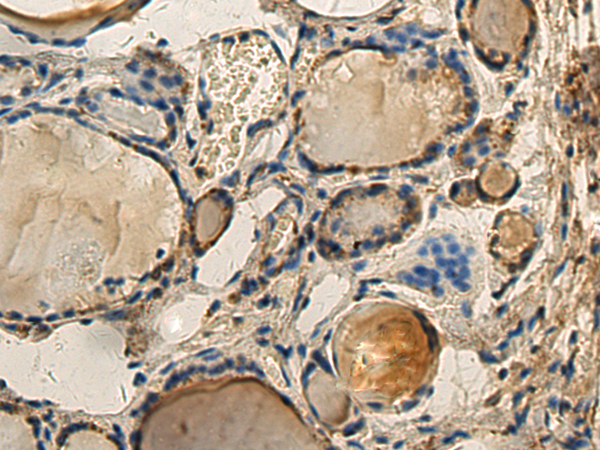

分类: 科研抗体货号: P01698别名: Gle2; MIG14; MRNP41; Mnrp41; dJ481F12.3; dJ800J21.1应用: WB,IHC反应种属: Human, Mouse, Rat